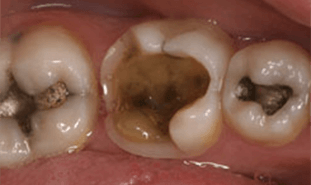

Before